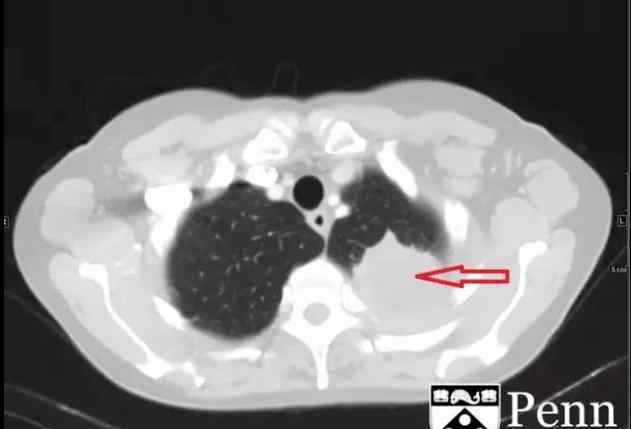

图4为胸部CT肺窗,显示左肺尖占位性病变,周围有毛刺影,局部及胸膜分解不清

胸部CT显示左肺尖是一个具有分叶和中央坏死区的占位性病变,与邻近胸膜无法区分,大小约为4.7×4.9×3.2cm,无明显骨转移征象。左侧锁骨上和左侧肺门上淋巴结肿大。

CT:平片CT可以用来确认平片上的高密度影。此外,它还可以用于评估骨骼受累。平片对肺、胸膜、胸壁和上腹部肿瘤转移的诊断价值有限。增强CT对评估血管受累和淋巴结受累非常有用。

图4为胸部CT肺窗,显示左肺尖占位性病变,周围有毛刺影,局部及胸膜分解不清

胸部CT显示左肺尖是一个具有分叶和中央坏死区的占位性病变,与邻近胸膜无法区分,大小约为4.7×4.9×3.2cm,无明显骨转移征象。左侧锁骨上和左侧肺门上淋巴结肿大。